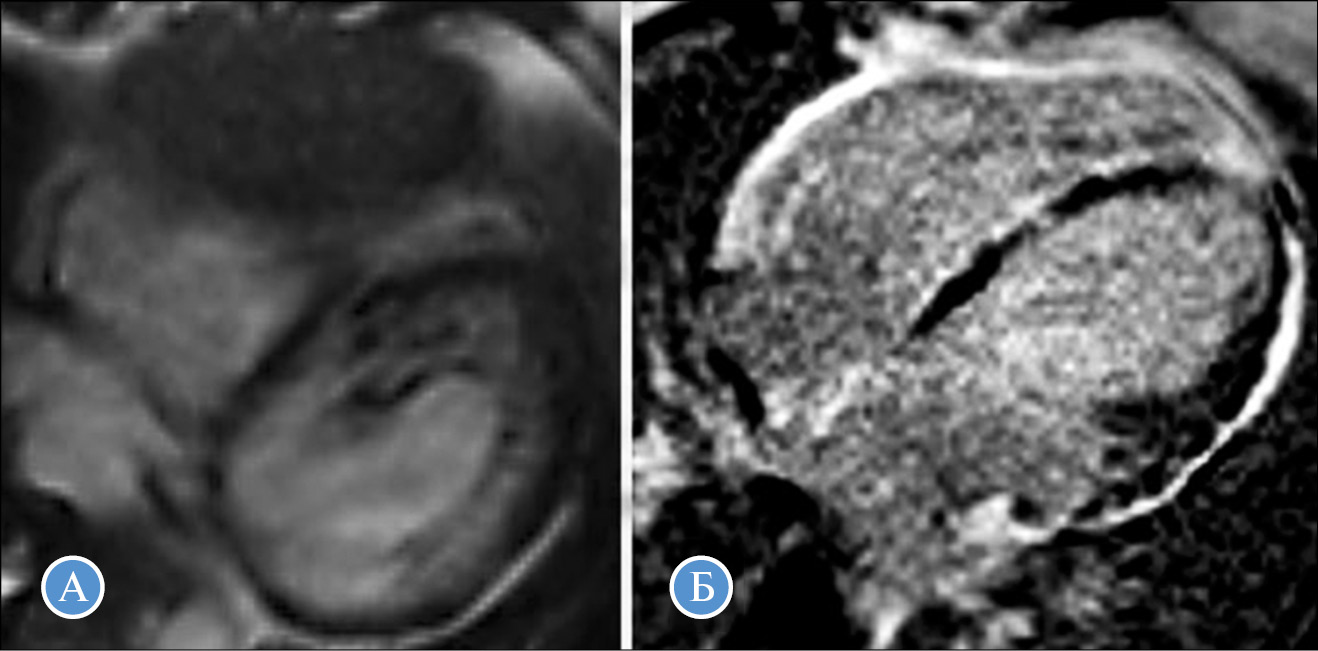

Рис. 2. МРТ сердца пациентки с сочетанием аритмогенной дисплазии правого желудочка и некомпактного миокарда левого желудочка и мутацией c.1141-2A>G в гене DSP (пробанд № 4).

А — некомпактный слой миокарда левого желудочка; Б — выраженная дилатация правого желудочка и отсроченное контрастирование в миокарде обоих желудочков и межжелудочковой перегородке со стороны правого желудочка (сопутствующий миокардит, верифицированный с помощью биопсии миокарда). Исследование выполнено в НЦССХ им. А.Н. Бакулева